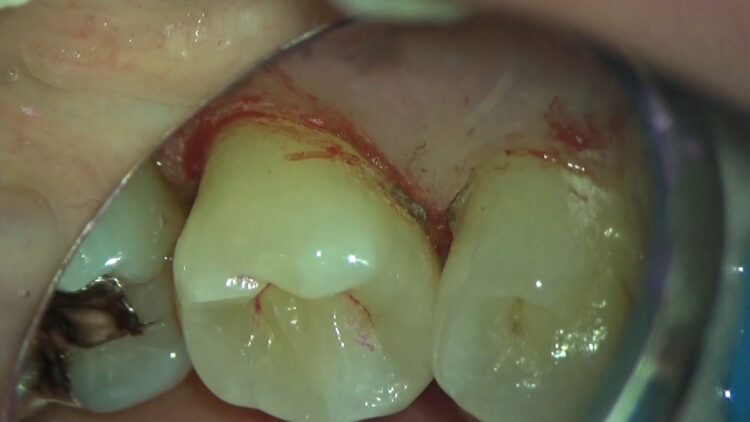

画像説明

歯周専門治療中に歯石除去をするところです。

黒く色づいている歯石が両サイドの歯にくっついています。